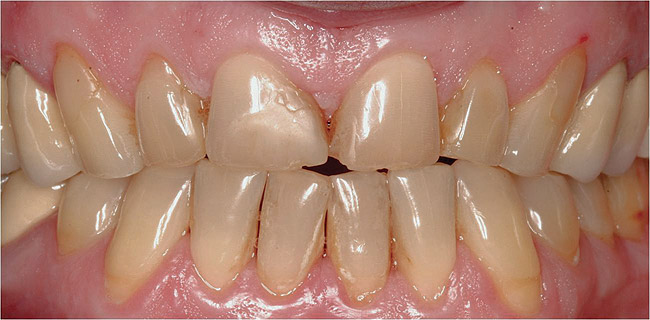

Figure  11  Loss of tooth enamel and translucency, resulting in yellowing of teeth.

Figure 11